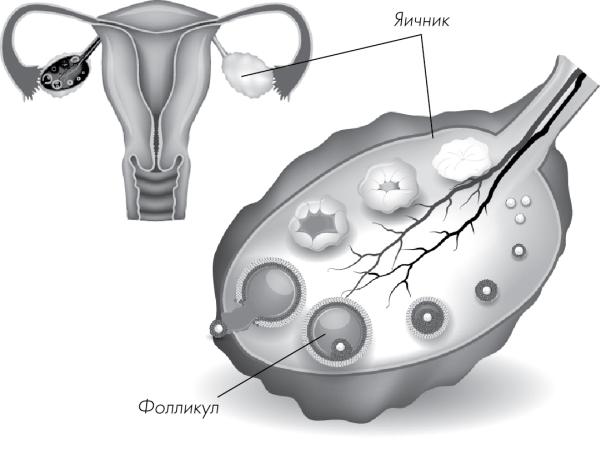

Созревание фолликула в яичнике: этапы и процессы